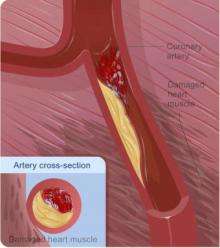

| Diagram of a myocardial infarction (2) of the anterior wall of the heart after blockage (1) of a branch of the left coronary artery (LCA). In the diagram, RCA is the right coronary artery. | |